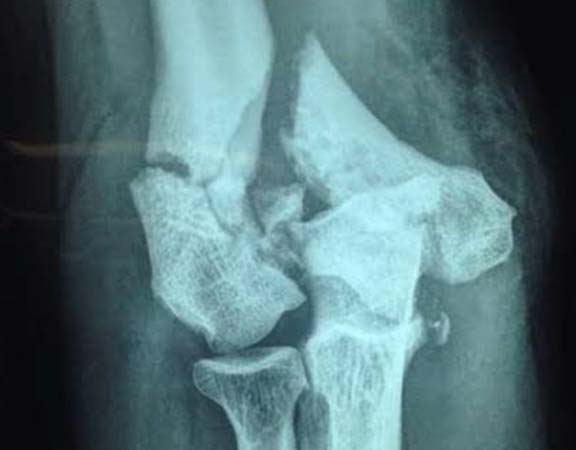

Fraturas do cotovelo

O cotovelo é composto por três ossos: o úmero, ulna e o rádio. As Fraturas do Cotovelo podem acontecer nesses três locais, isoladamente ou em conjunto, acompanhadas ou não por alguma lesão ligamentar ou de nervo. Assim como todas as fraturas, as de cotovelo se dão quando há um rompimento em um ou mais locais do osso. As que ocorrem nessa articulação são: a fratura da cabeça do rádio, a mais comum entre todas; fratura da porção distal do úmero e do olécrano (parte de trás do cotovelo, parte da ulna). As fraturas podem ocorrer em decorrência de uma queda com o braço estendido ou por traumas de alto impacto, como os acidentes automobilísticos. Dor, edema, hematoma e deformidade são os principais sintomas da doença. O diagnóstico e feito através da realização de radiografia e pela tomografia computadorizada. O tratamento pode ser realizado com imobilização gessada para aquelas fraturas bem alinhadas e o tratamento cirúrgico para as fraturas desalinhadas.